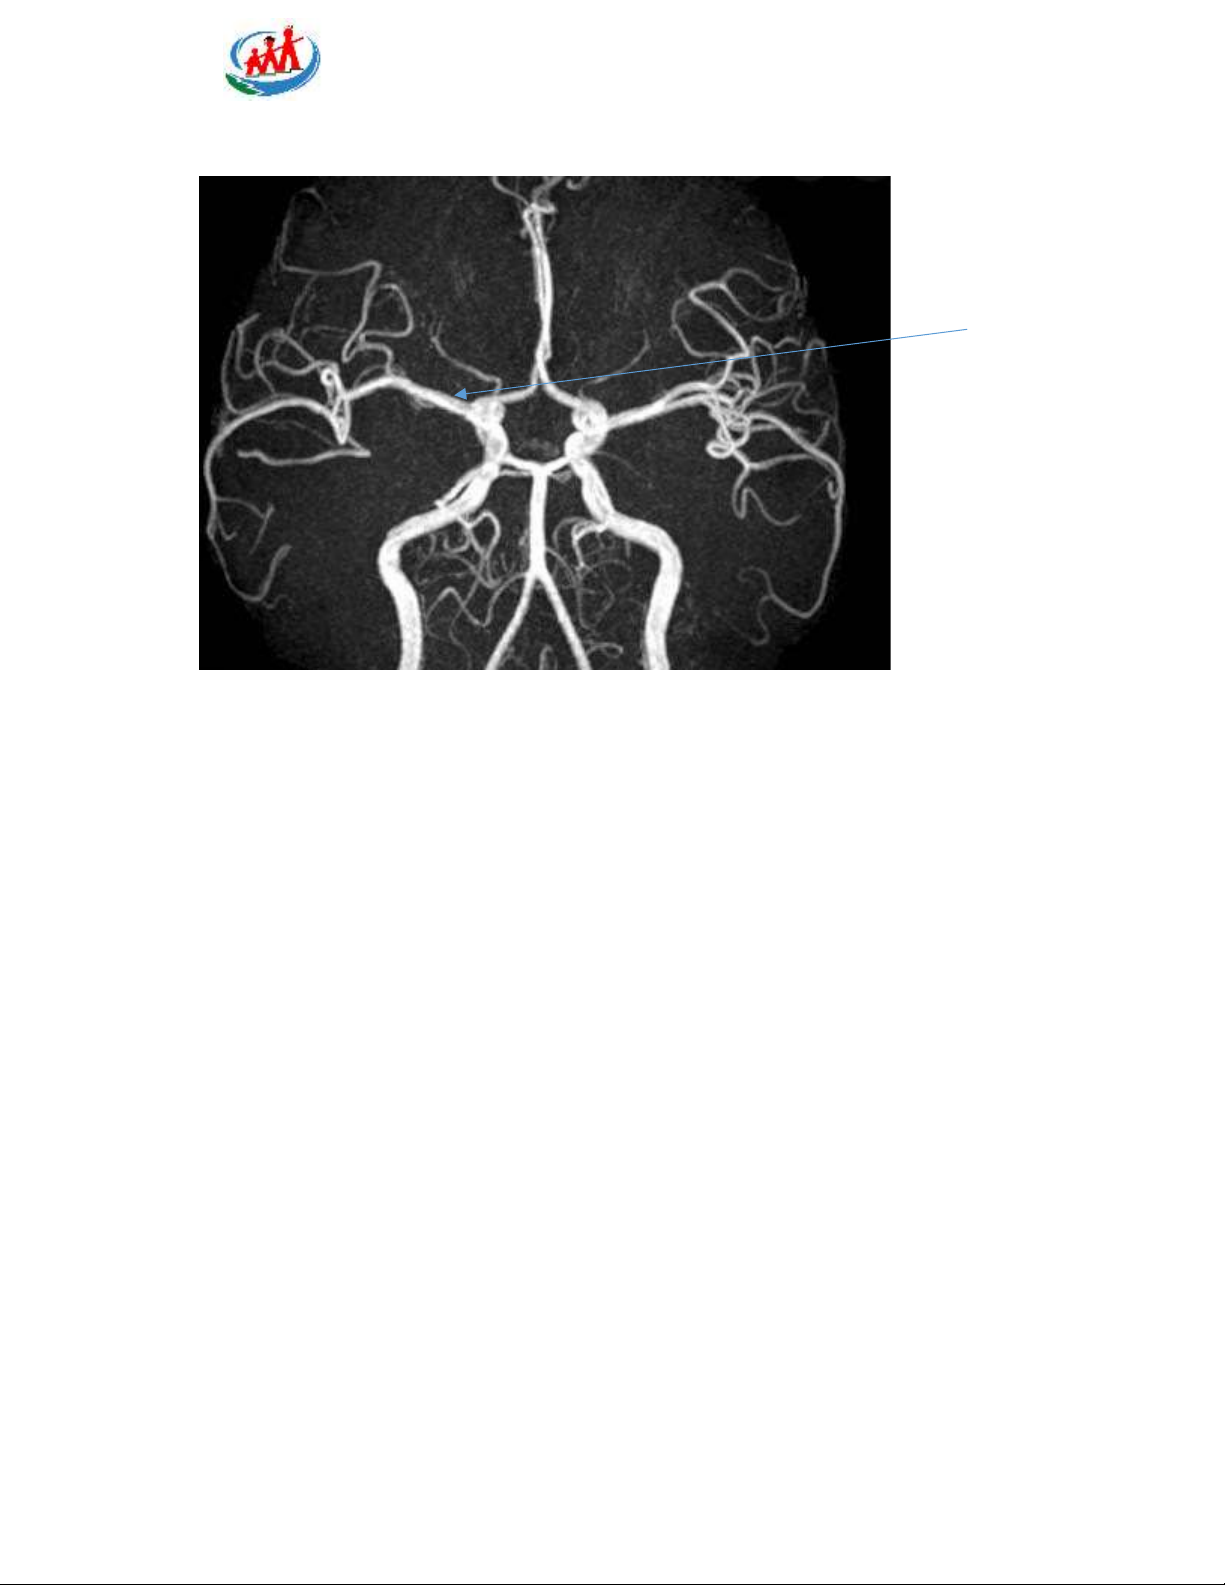

Câu 5: Mũi tên mô tả động mạch nào?

A. Động mạch não trước

B. Đông mạch não giữa

C. Động mạch não sau D. Động mạch thông sau P a g e 3 | 15